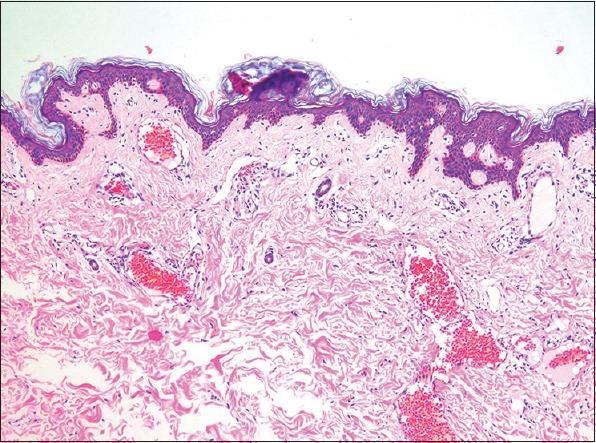

Dermoscopy of Angiokeratoma.

Indian Dermatol Online J. 2018 Mar-Apr;9(2):141-142. doi: 10.4103/idoj.IDOJ_278_17.